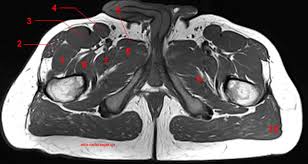

Axial pelvis ct axial femur ct axial femur ct axial knee ct. The muscles of the pelvis, hip and buttock anatomical chart shows how each muscle in this area of the body works with the others, and the various minor systems within the major ones. Hepatocellular carcinoma or liver cancer. The floor is composed of two muscular layers, the levator ani/coccygeus complex and. There are many muscles that form the pelvic floor, including puborectalis, pubococcygeus, iliococcygeus and coccygeus. Pelvic floor muscles that are located wholly within the pelvis. Almost every movement in the body is the outcome of muscle contraction. The muscles are connected with the bones. Learn about anatomy muscles pelvis with free interactive flashcards. The gastrocnemius muscle is a complex muscle that is fundamental for walking and posture. Attached to the bones of the skeletal system are about 700 named. Muscles, connected to bones or internal organs and blood vessels, are in charge for movement. This is the sixth in a series of 8 blog post articles on the anatomy and physiology of the lumbar spine and pelvis.

Axial pelvis ct axial femur ct axial femur ct axial knee ct. The floor is composed of two muscular layers, the levator ani/coccygeus complex and. 0835 lotze anatomy of the pelvic floor. organs and structures of the female pelvis. There are many muscles that form the pelvic floor, including puborectalis, pubococcygeus, iliococcygeus and coccygeus.

Radiological Anatomy X Ray Ct Mri Kenhub from thumbor.kenhub.com Their main function is contractibility. Axial pelvis ct axial femur ct axial femur ct axial knee ct. Ct anatomy of the pelvis. This mri male pelvis axial cross sectional anatomy tool is absolutely free to use. Rib thorax lumbar pelvis sacrum coccyx femur fibula tibia. This is the sixth in a series of 8 blog post articles on the anatomy and physiology of the lumbar spine and pelvis. The muscles of the pelvis form its floor. Included within the chart are gorgeous illustrations of the pelvic diaphragm, sphincter muscles, gluteus maximus.

Ischial tuberosity which flexor of the knee attaches here?